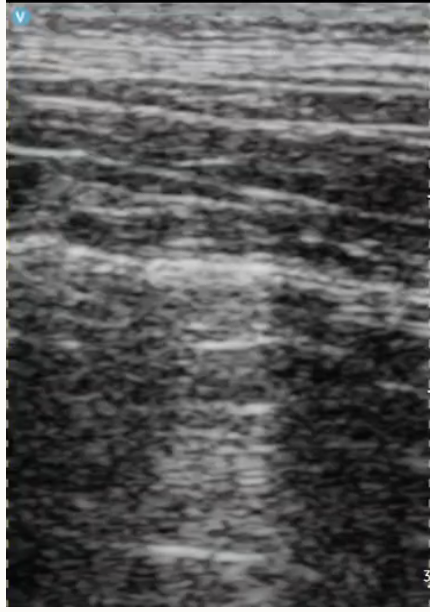

What does a normal lung ultrasound look like?

A

What is going on in this lung ultrasound

What can you see in this lung ultrasound?

Pulmonary contusions (B-lines)

Pleural effusion